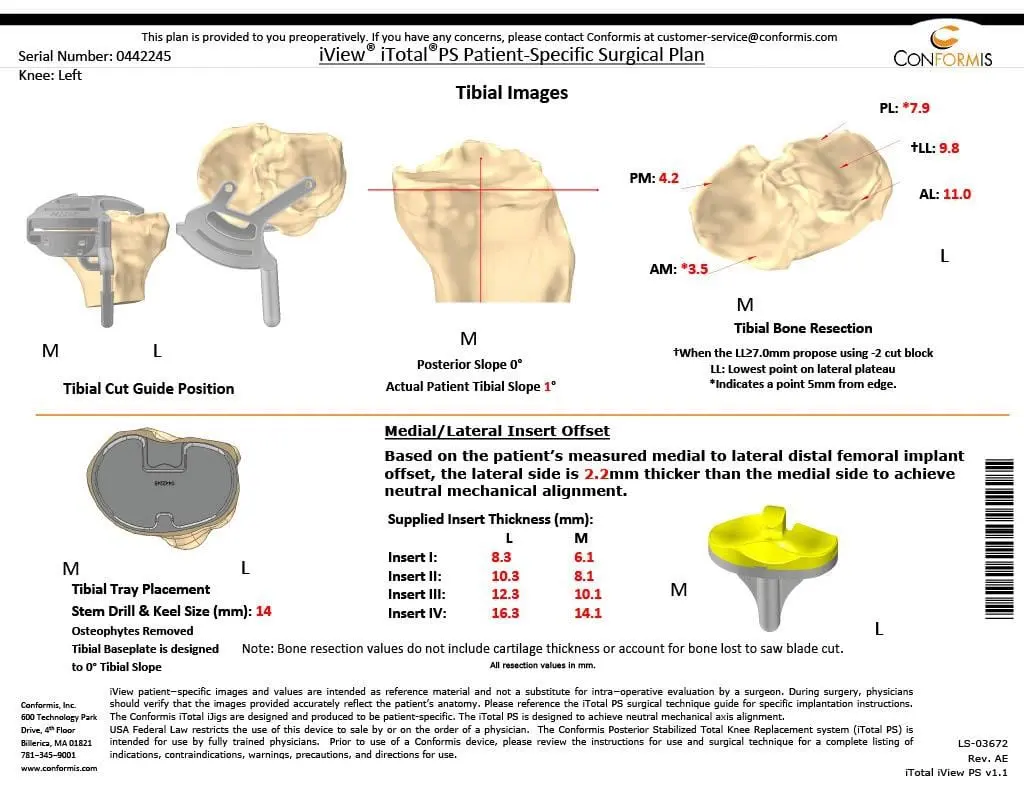

Patient detailed anatomy and biomechanics axis were obtained from a preoperative CT scan. The data obtained was used to construct custom implants. The custom implants were unique for the patient’s anatomy. Disposable 3D constructed jigs were made for accurate bone cuts. A preoperative plan was formed to aid the surgeon in the operation.

Preoperative Surgical plans